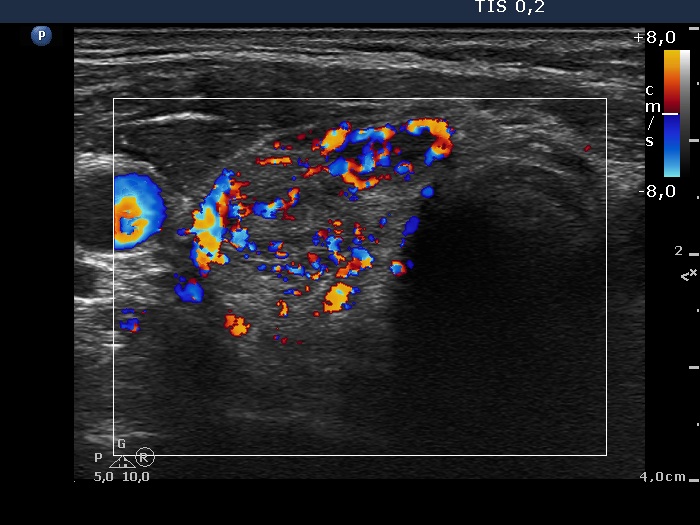

Ultrasonography. The thyroid lobes were composed of hypoechoic discrete areas. The vascularity of the thyroid was increased.